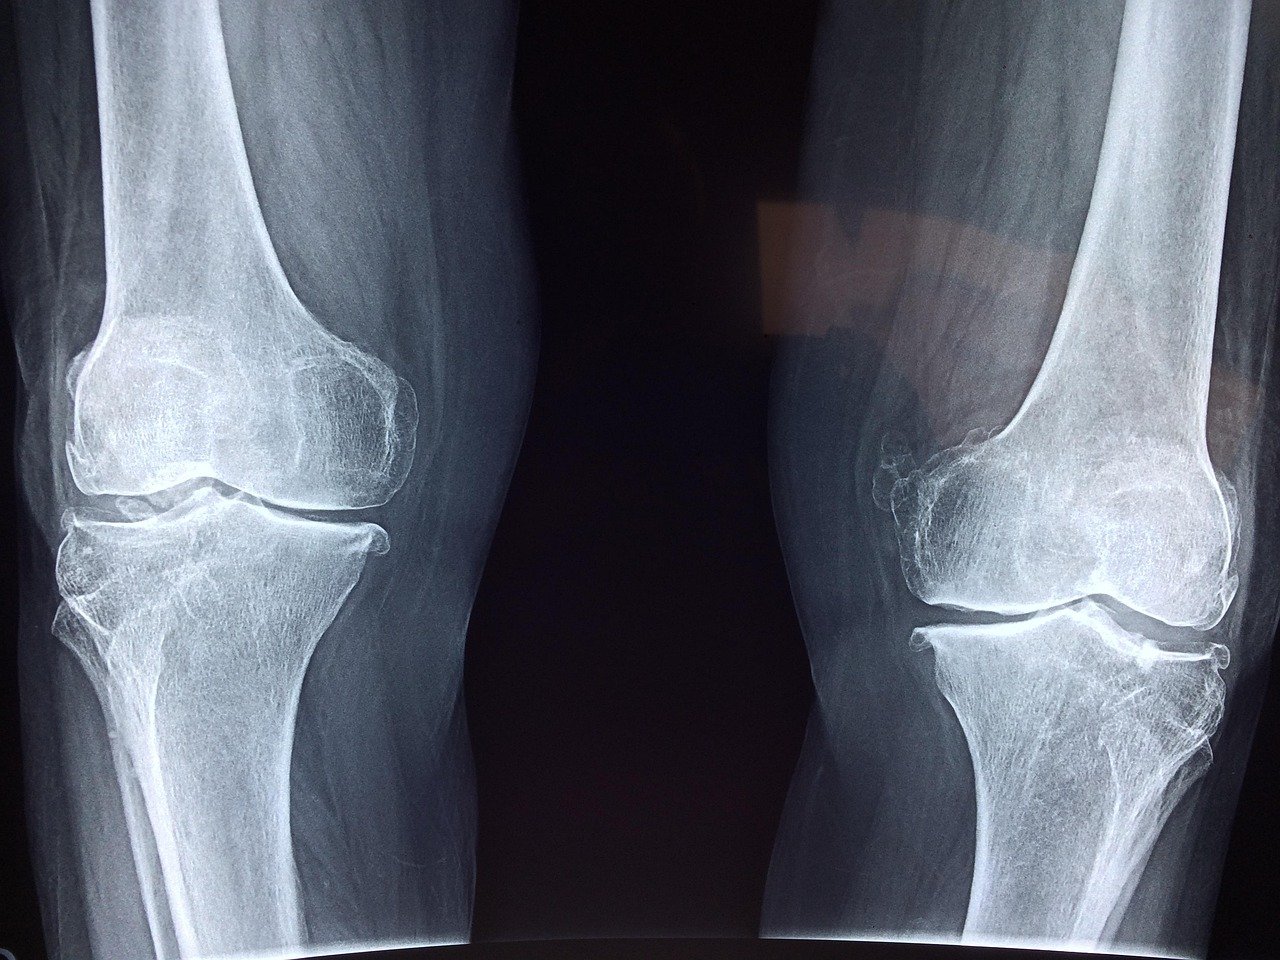

- Joints: Patients with osteoarthritis and general joint degeneration, stem cell therapies are specifically designed to promote the body’s innate capacity to heal damaged cartilage in joints such as the hips, ankles, and wrists.

- Knees:Â Individuals with injuries, including a torn meniscus or Grade I or II ACL injuries, can find relief through our specialized stem cell treatments for knee pain.